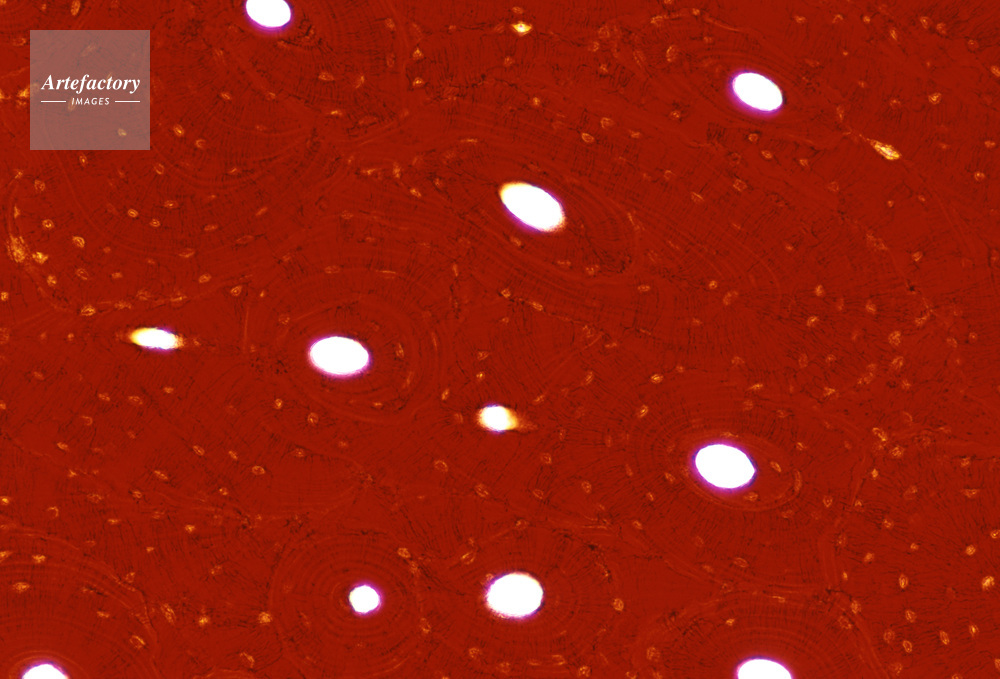

| 作品タイトル | 顕微鏡写真 | モデルリリース | なし | |

| キャプション | 硬骨,人間,100倍,横断面 | 制限事項 | ||

| ソース | ピクセル数 | 5556px × 3772px | ||